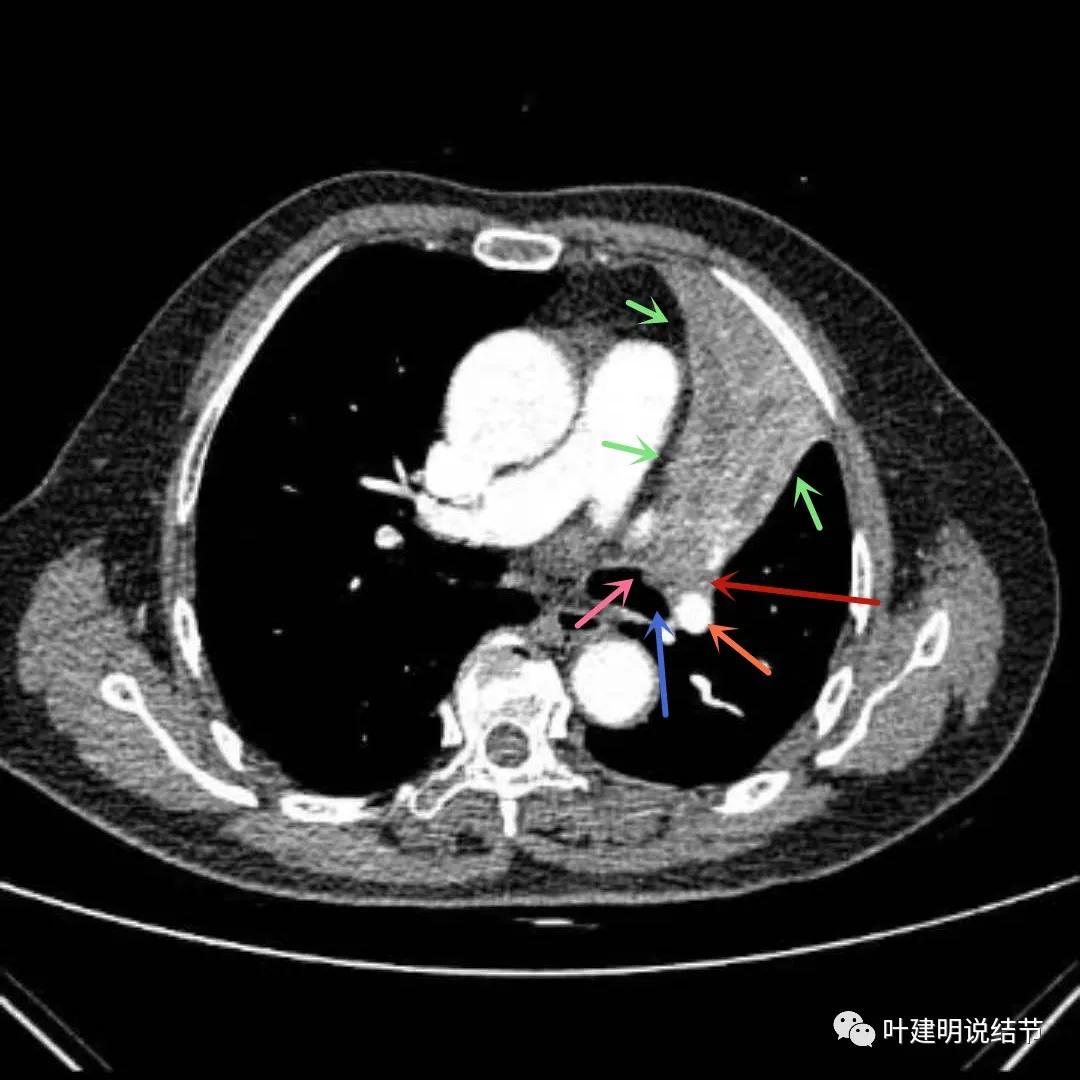

上图绿色箭头所指区域考虑为肺不张,红色示肿瘤处,黄色箭头示肿瘤区域内有坏死低密度,桔色细箭头所指处是被肿瘤包绕的肺动脉分支起始部,粗桔色箭头示肺动脉与肿瘤间紧密愈着,考虑有侵犯肺动脉

上图绿色箭头所指区域考虑为肺不张,红色示肿瘤处且有不均质与膨胀性,桔色细箭头所指处是被肿瘤包绕的肺动脉分支起始部,粗桔色箭头示肺动脉与肿瘤间紧密愈着,考虑有侵犯肺动脉